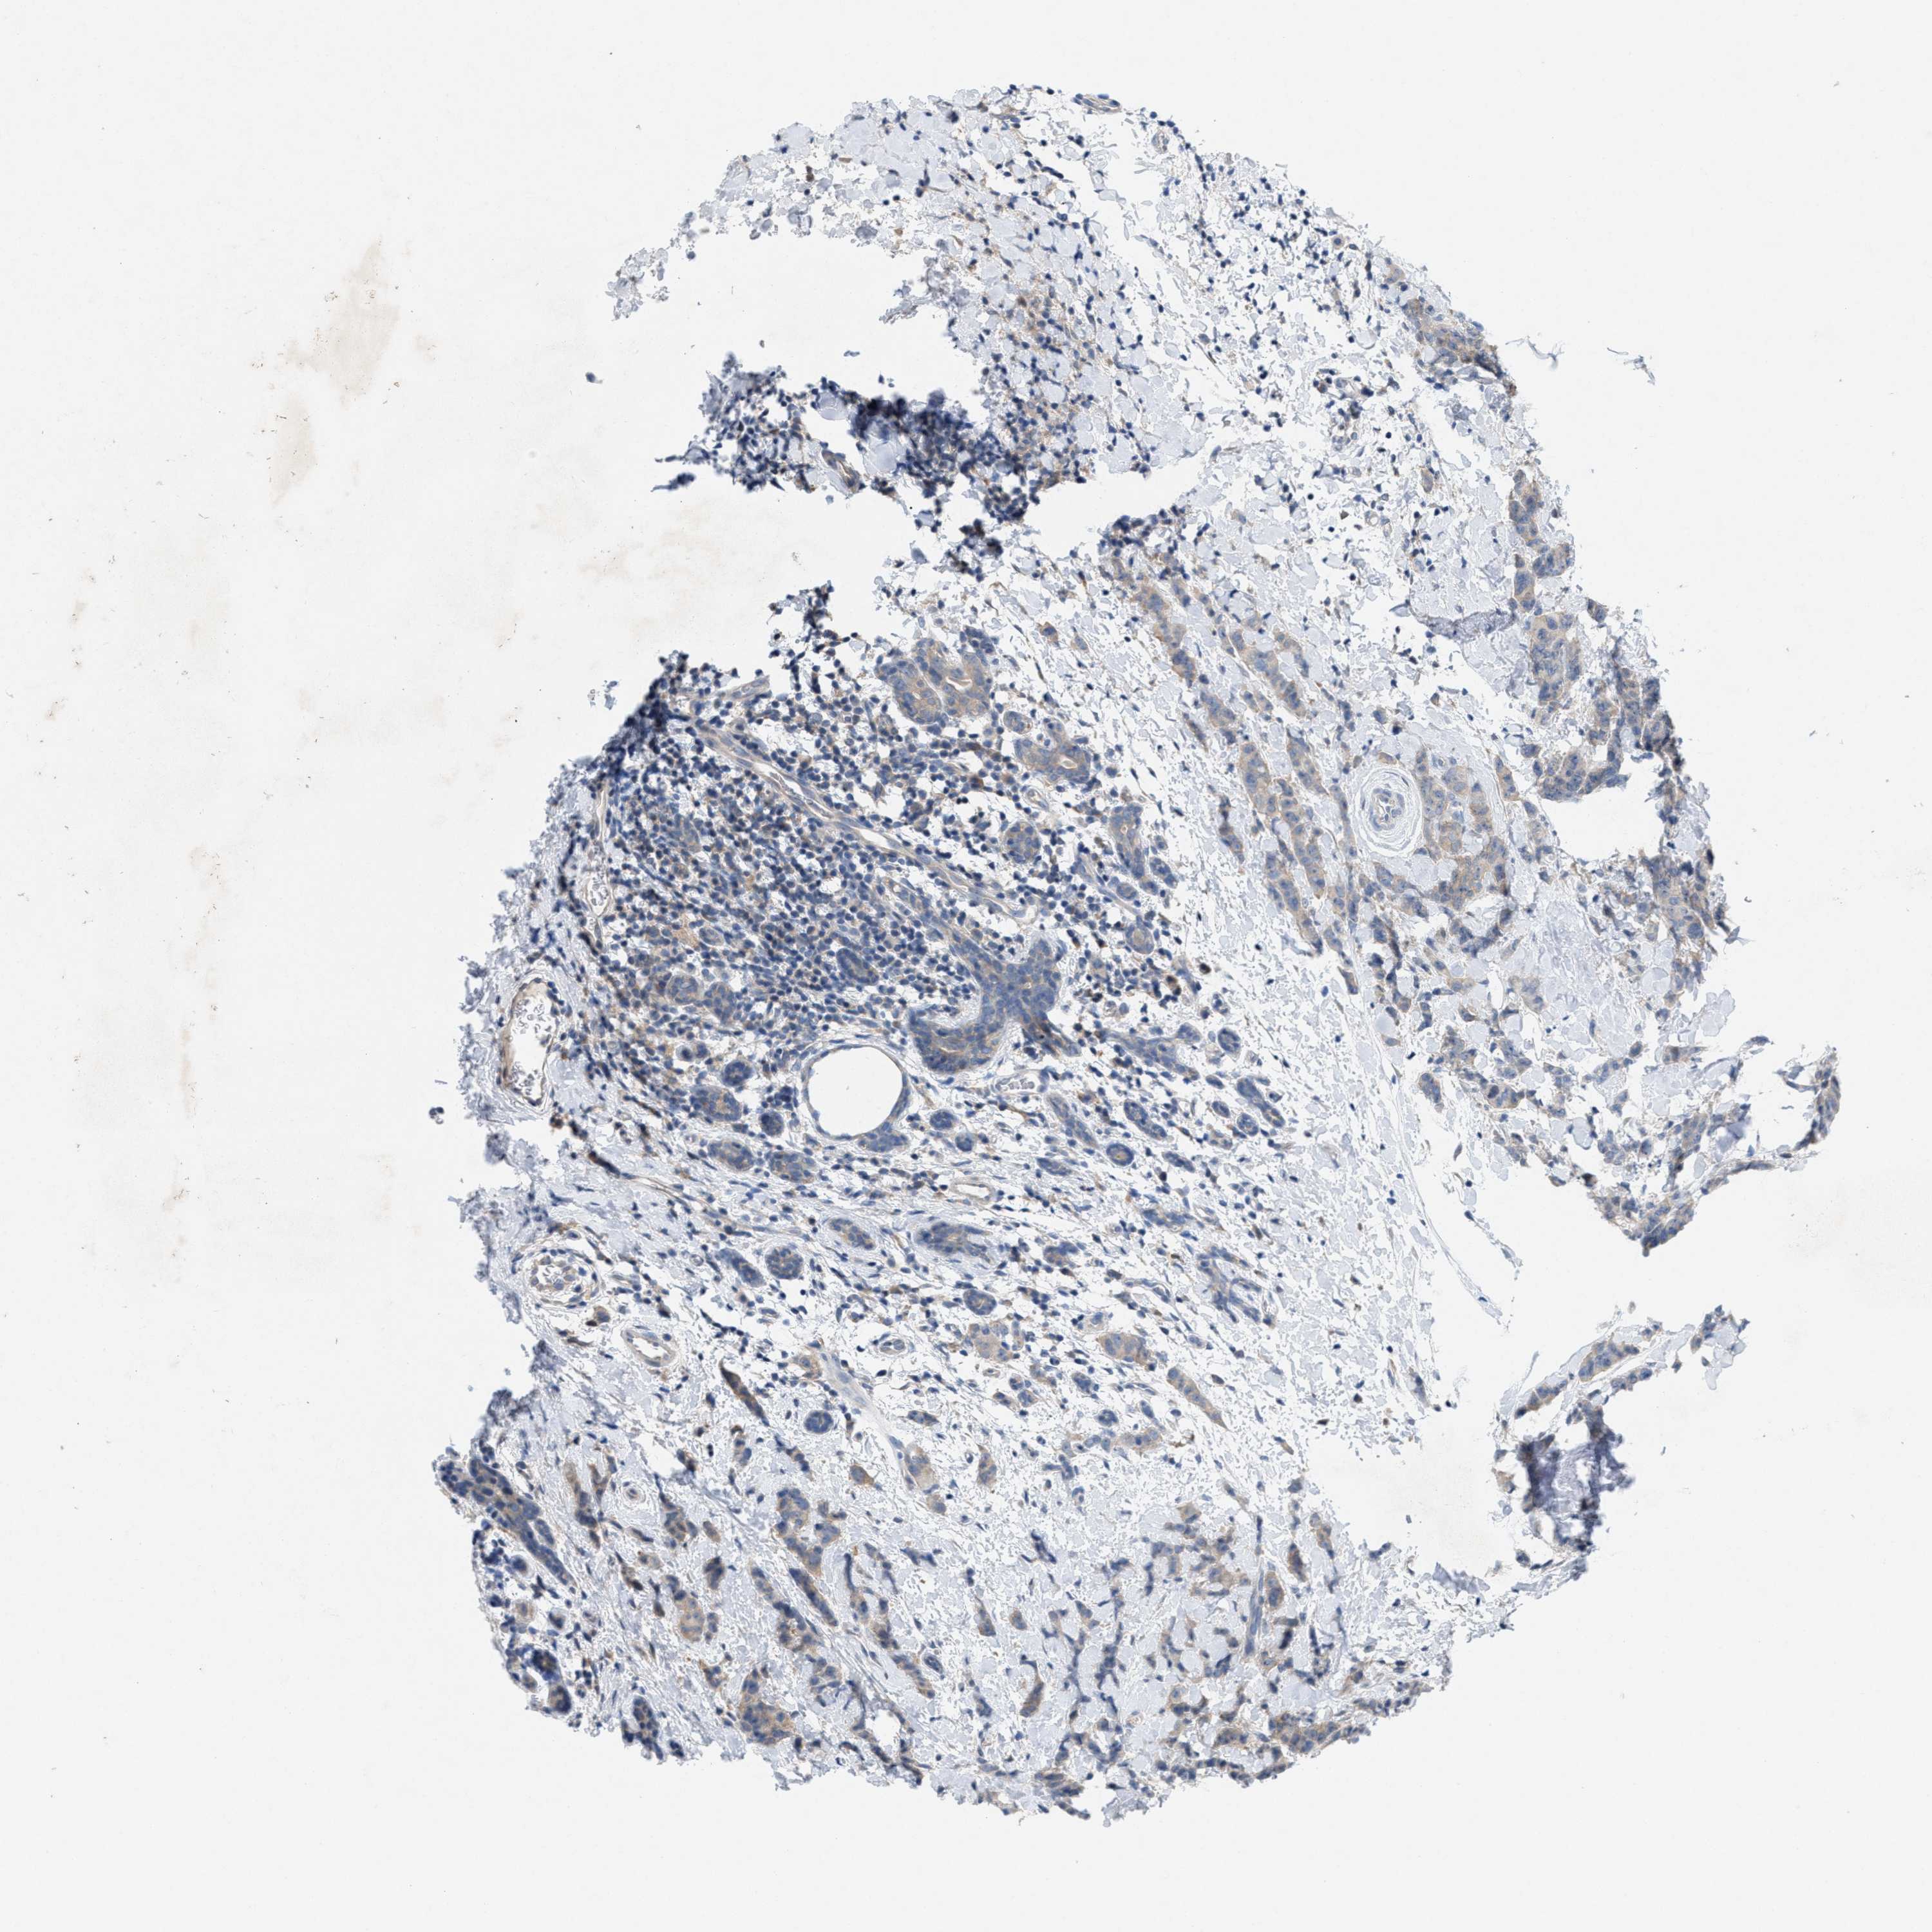

CANCER BREAST CANCER Show tissue menu

BRCA TCGA BRCA VALIDATION PROTEIN EXPRESSION

ANTIBODIES

AND

VALIDATION